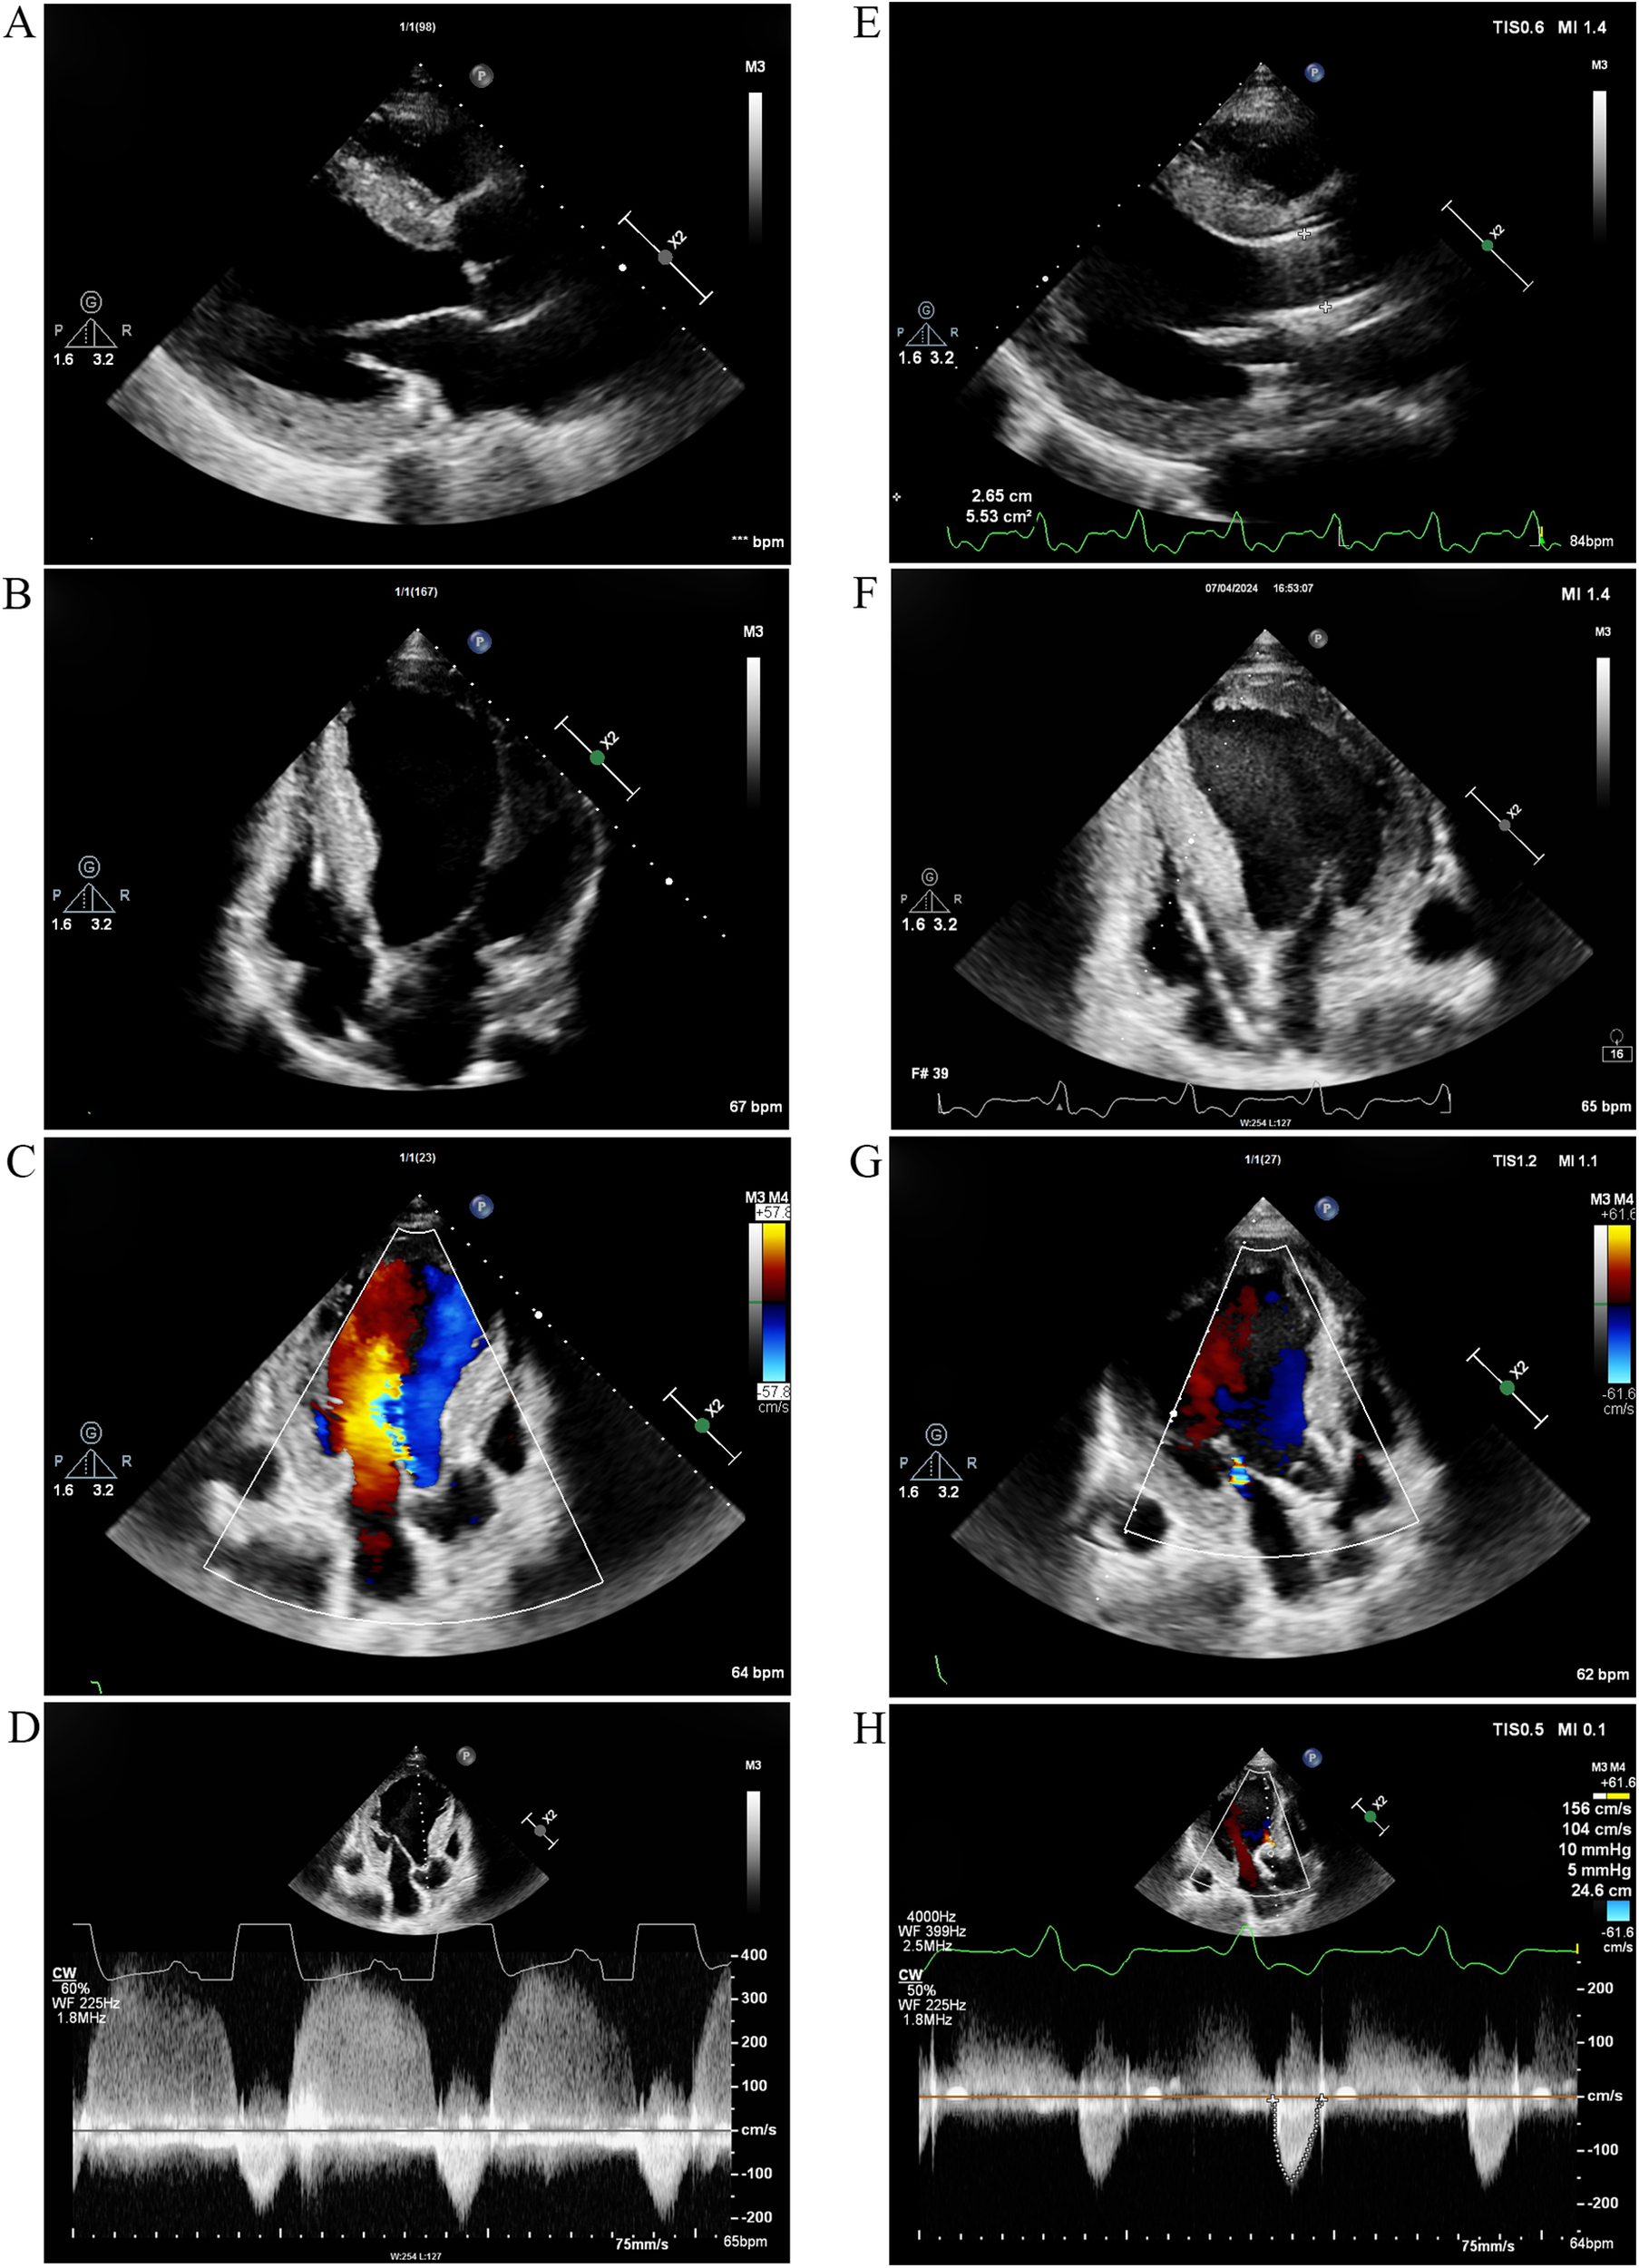

At the beginning of 2022, ERT was initiated. The patient received α-galactosidase at a dosage of 0.2 mg/kg every other week. Unfortunately, in May 2024, he developed symptoms of heart failure, including exertional dyspnea and orthopnea. The N-terminal pro-B-type natriuretic peptide (NT-proBNP) concentration was 1,746 pg/ml. TTE indicated significant left ventricular enlargement, with the left ventricular ejection fraction decreasing to 27.4% (Figures 4A,B). Echo enhancement of the aortic valve was identified via two-dimensional echocardiography and severe aortic regurgitation on Doppler imaging (Figures 4C,D). The patient underwent transcatheter aortic valve replacement (TAVR) at Zhongshan Hospital (Shanghai, China) 1 month later. He had a smooth recovery, and his heart failure symptoms improved significantly postoperatively (Figures 4E–H) (Table 1).

Figure 4

TTE 2 years after ERT and 1 month after TAVR. (A) Parasternal long-axis view of the left ventricle and (B) Apical four-chamber view 2 years after ERT. The left ventricle was significantly enlarged, and the left ventricular ejection fraction decreased to 27.4%. (C) Color Doppler flow imaging and (D) continuous wave Doppler 2 years after ERT revealed echo enhancement of the aortic valve and severe aortic regurgitation. (E) Parasternal long-axis view and (F) apical four-chamber view demonstrated improvement in left ventricular chamber diameter and enhancement of cardiac systolic function 1 month after TAVR. (G) Color Doppler flow imaging and (H) Continuous wave Doppler indicated that aortic regurgitation improved 1 month after TAVR. TTE, transthoracic echocardiography; ERT, enzyme replacement therapy; TAVR, transcatheter aortic valve replacement.